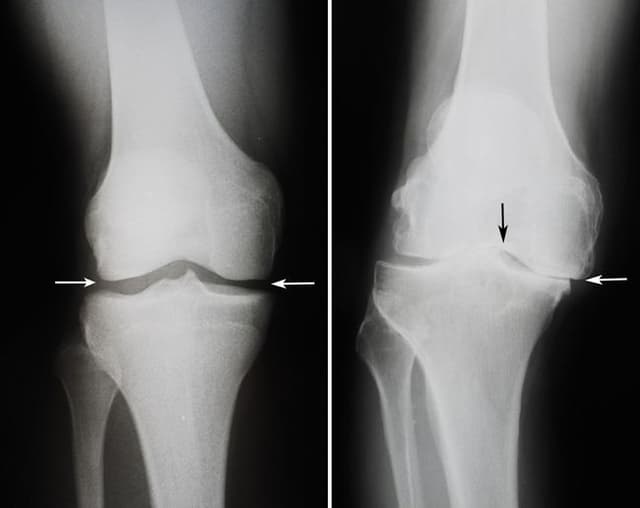

Knee Arthroscopy

Knee arthroscopy is a minimally invasive surgical procedure used to diagnose and treat a variety of knee problems. It's a same-day surgery, meaning you typically go home on the same day. During the procedure, your surgeon makes small incisions around your knee and inserts a tiny camera called an arthroscope.